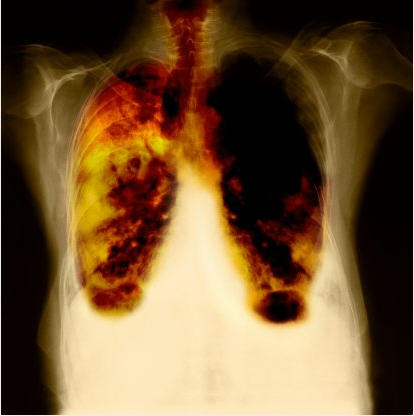

Sëmundja asbestoza shkakton një fryrje dhe korëzim të indeve të mushkërive, që rrit ndjeshëm mundësinë e kancerit në mushkëri. Në vitin 1930, Parlamentit britanik iu paraqit një raport ku argumentohej shkencërisht se asbestoza lidhej me thithjen për një kohë të zgjatur të pluhurit të asbestit.